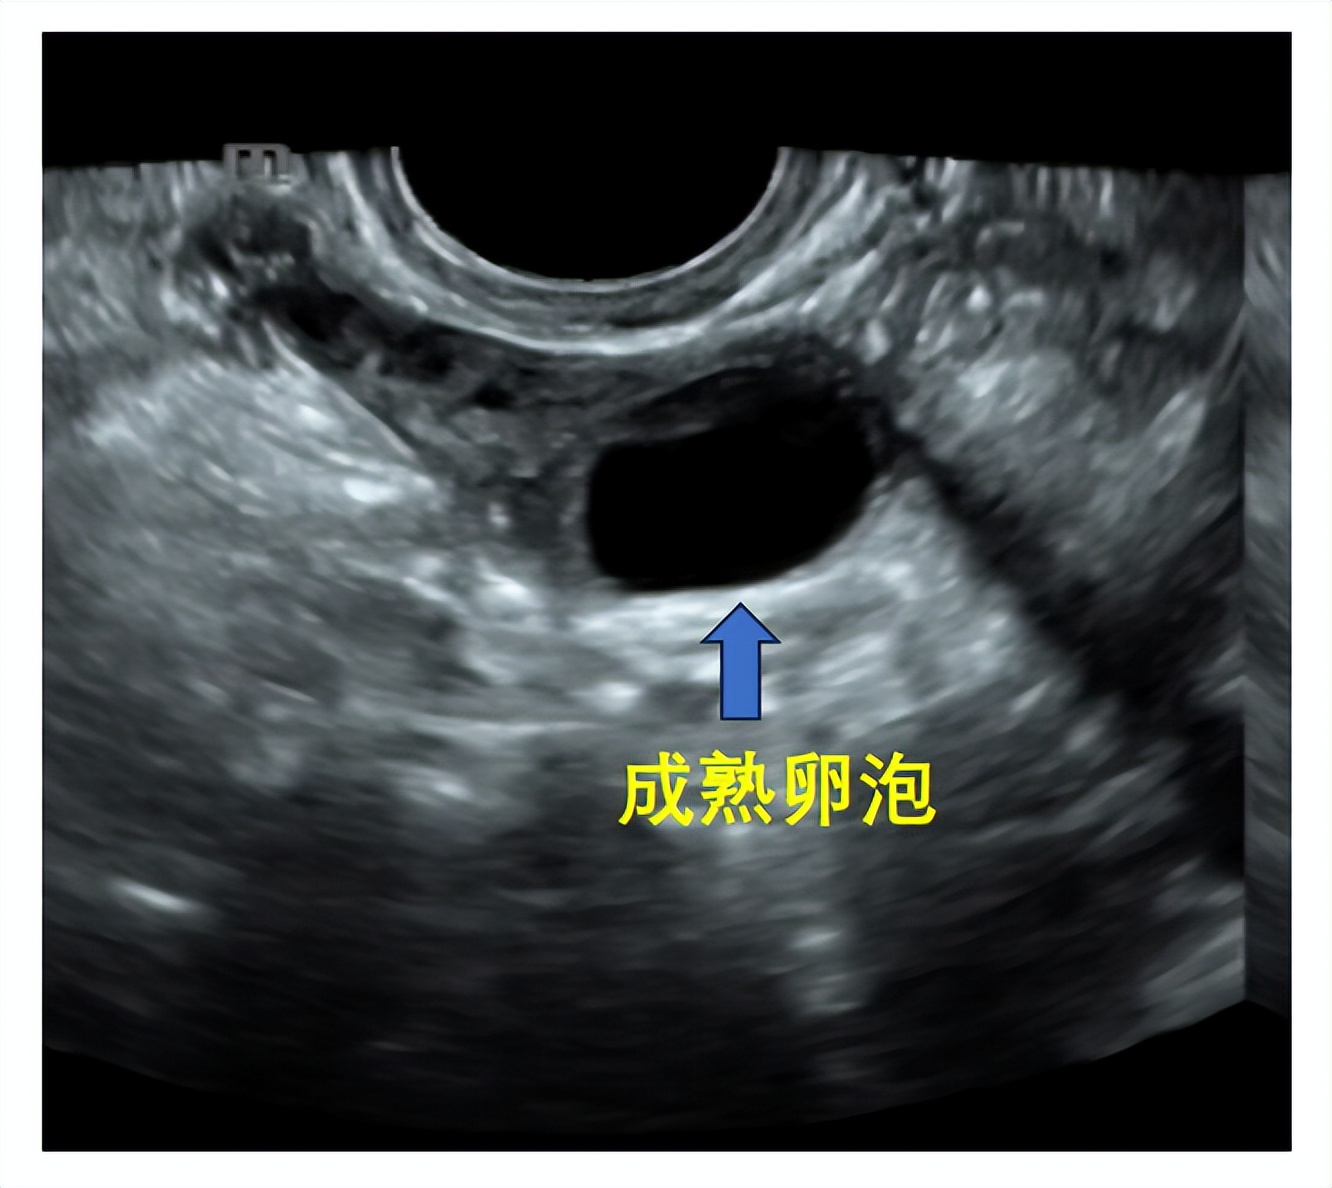

成熟卵泡(月经周期14天左右):卵泡直径达到18-25mm时,外形饱满呈圆形或椭圆形,内壁薄而清晰,位置移向卵巢表面并向外突出,如果卵泡一侧内壁上探及卵丘(出现率约20%),表现为细小点状高回声 ,意味着排卵过程将在24小时内开始。